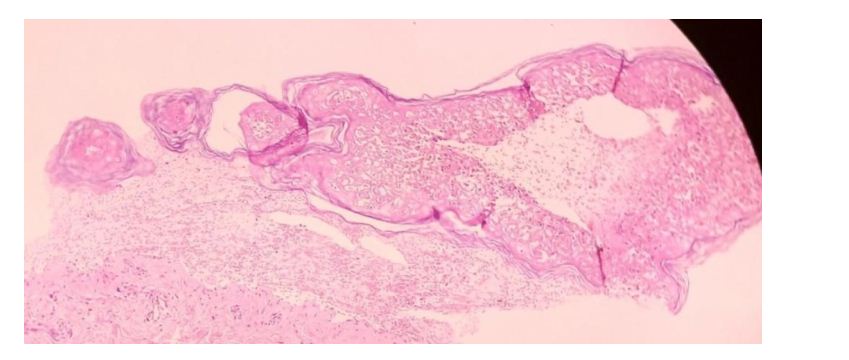

Her serology revealed 3+, homogenous ANA and positive anti ds DNA and low complements. There was evidence of renal involvement in the form of new onset hypertension, subnephrotic range of proteinuria, elevated blood urea and serum creatinine. Her 2D Echo showed global hypokinesia with dilated left atrium (LA), severe left ventricle (LV) dysfunction, dilated, plethoric IVC. She also had serositis (pleural and pericardial). Her skin biopsy showed orthokeratosis of epidermis and transepidermal coagulative necrosis with exocytosis composed of lymphocytes, eosinophils and nuclear debris (Figure 3). Complete detachment of epidermis was seen. Dermis showed thin walled vessels with perivascular lymphoid infiltrate. Skin biopsy features were consistent with TEN.

Figure 3: Skin biopsy consistent with features of TEN.